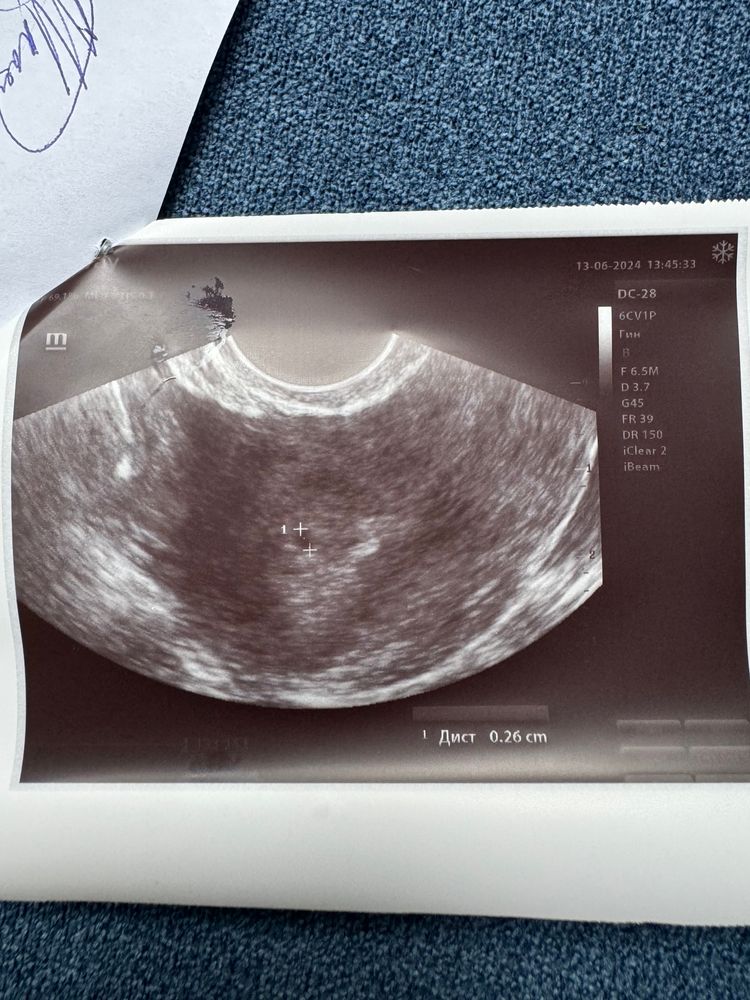

Плохое плодное яйцо